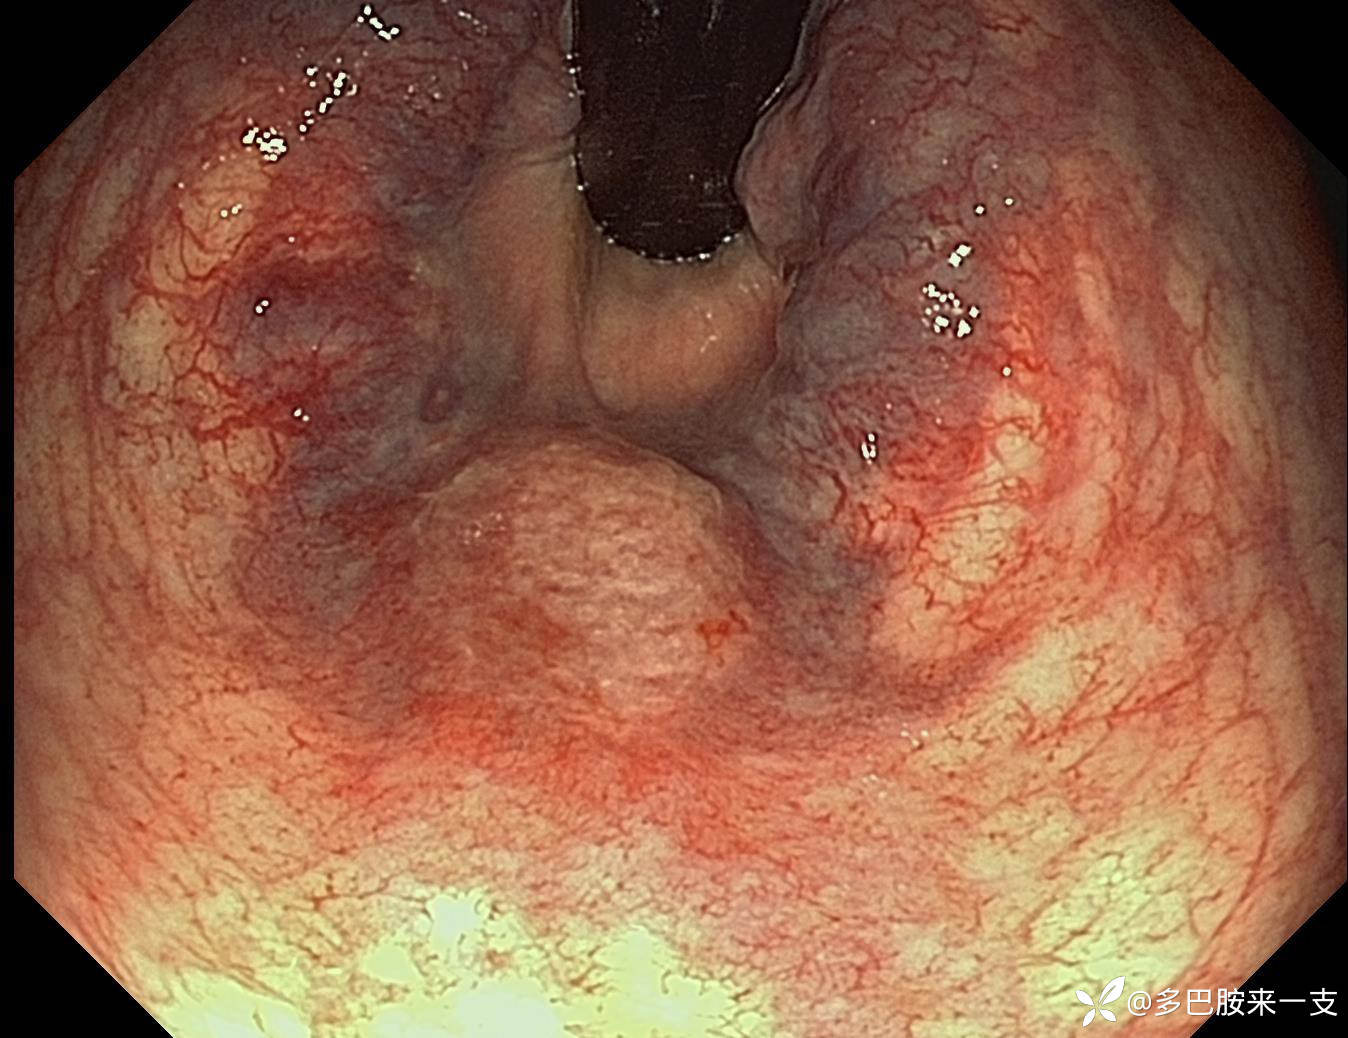

【检查】回肠末端到直肠均未见异常。镜下如图可见稍隆起粘膜,色偏白,水肿,表面粗糙,边缘见渗血点。NBI图没踩上。